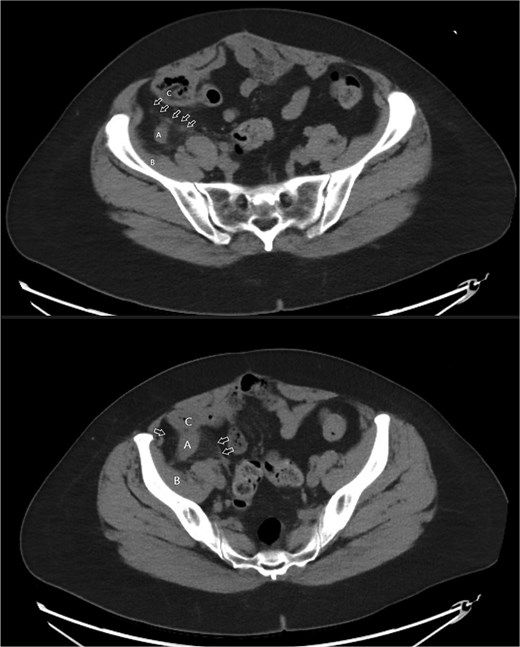

A 58-year-old female with a history of ovarian cancer, status post total abdominal hysterectomy, bilateral salpingo-oophorectomy, and omentectomy, presented with a 1-week history of right lower quadrant and right pelvic abdominal pain. Her labs were unremarkable. A CT scan of the abdomen and pelvis revealed a distended, fluid-filled appendix measuring 1.7 cm in diameter, with associated mesenteric infiltration and several small lymph nodes in the right lower quadrant, consistent with acute appendicitis (Fig. 1). The surgeon’s review of the scan was suspicious of retrocecal appendix (Fig. 2).

Coronal image CT scan with IV contrast with arrows denoting appendix in proximity to iliacus space. (A) Appendix.